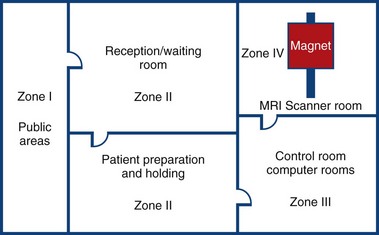

MRI Zone 4

Zone 4: Magnet Room

Authorised access only

The scan room door is always locked when unattended

Metal is removed

Danger signs

When the scan room door is opened, the MRI Safety barrier must be implemented at all times by MRI personnel

Forms for safety and consent

MRI Zone 3

Zone 3: Control Room

All metal removed

Locks on doors

Caution signs

Authorised access only

MRI Zone 2

Zone 2: Patient Screening and Prep

Patients and families undergo screening and are cleared to enter the magnetic area

MRI Zone 1

Zone 1: Unrestricted area (public walkway)